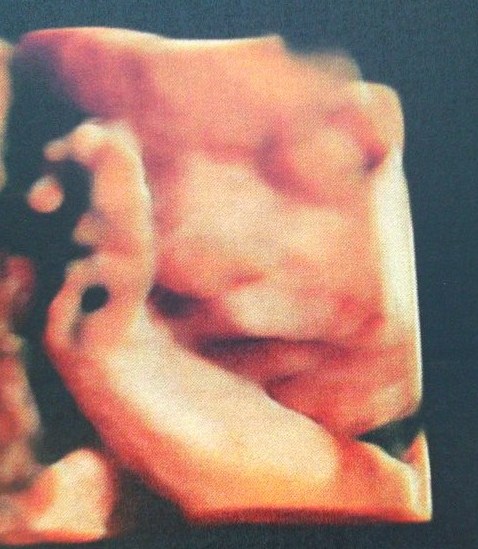

Dziewczyny, przepraszam, ale musze się pochwalićpatrzcie na te cudeńko ( zdjecia z tych trzecich prenatalnych)

Zobacz załącznik 716366Zobacz załącznik 716367